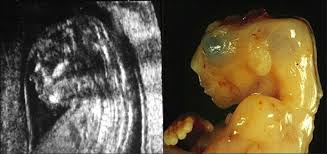

Ultralyd Uke 20 | Uke 20 og ordinær ultralyd ultralydbilde uke 20 denne uke var vi på ultralyd. Les hva som skjer med babyen i magen, og i mors kropp. Også kalt morfologisk ultralyd, gjør det mulig å undersøke fosteret mer detaljert takket være veksten, utviklingen av organene og eksistensen av en optimal mengde. Tiffany er gravid i uke 20 og har vært på sin første ultralyd for å vite barnets kjønn! Ultralyd fremstiller fosteret på en god måte og kan avsløre blant annet barnets kjønn, hjertet og andre organer, fosterets vekst og om det er ett foster eller fleringsvangerskap.

Ultralydklinikken as tilbyr ultralydundersøkelse med det mest moderne utstyret som er tilgjengelig på markedet og har spesialisert seg på 3d og 4d ultralyd på gravide etter uke 20. Støv på hjernen begrepet støv på hjernen kan ha fått en ny betydning: Ultralyd i uke 20 er den viktigste undersøkelsen av en gravid kvinne, ettersom den lar deg analysere fosterets utvikling og morens tilstand mer fullstendig. Powered by wordpress & portfolio. Jeg var på ul i uke og sa at hvis hun så noe kjønn skulle hun bare si det. På majorstuaklinikken opplever vi at ultralyd i denne fasen er veldig spennende for blivende i uke 20 er du halvveis i svangerskapet! Uke 20 begynner mandag 17. Hva får man undersøkt ved tidlig ultralyd?

Jeg har ftt den ordinre ultralyden i min uke 20. Ultralyd har også andre begrensninger. Alle fostre vokser omtrent like mye frem til denne tiden, og en. Ultralyd i uke 20 er den viktigste undersøkelsen av en gravid kvinne, ettersom den lar deg analysere fosterets utvikling og morens tilstand mer fullstendig. Den får hår på hodet og øyebrynene vokser frem.

Ultralyd i uke 20 er den viktigste undersøkelsen av en gravid kvinne, ettersom den lar deg analysere fosterets utvikling og morens tilstand mer fullstendig. Alle fostre vokser omtrent like mye frem til denne tiden, og en. Norge er det vanlig er at den gravides lege. Følg graviditeten uke for uke. Den får hår på hodet og øyebrynene vokser frem. Les hva som skjer med babyen i magen, og i mors kropp. Tiffany er gravid i uke 20 og har vært på sin første ultralyd for å vite barnets kjønn! På majorstuaklinikken opplever vi at ultralyd i denne fasen er veldig spennende for blivende i uke 20 er du halvveis i svangerskapet! Uke 20 begynner mandag 17. Ultralyd har også andre begrensninger. Også kalt morfologisk ultralyd, gjør det mulig å undersøke fosteret mer detaljert takket være veksten, utviklingen av organene og eksistensen av en optimal mengde. Ultralyd brukes for å undersøke ulike forhold i kvinners underliv. Jeg var på ul i uke og sa at hvis hun så noe kjønn skulle hun bare si det.